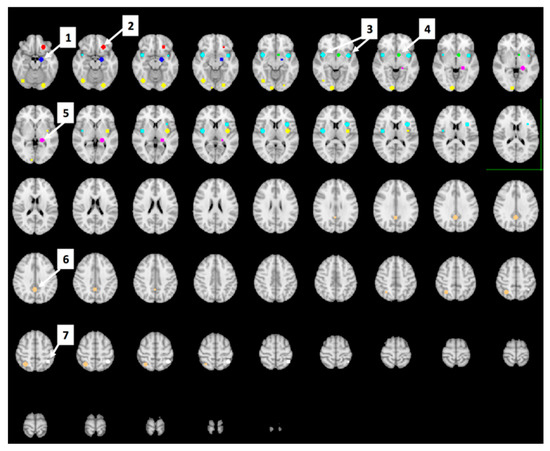

3.6. Whole Brain Analyses of Activity during Food Valuation Period

3.7. Drink Effects on Whole Brain Activity Associated with Food Valuation

3.8. Bid-Correlated Brain Activity during Food Valuation Period